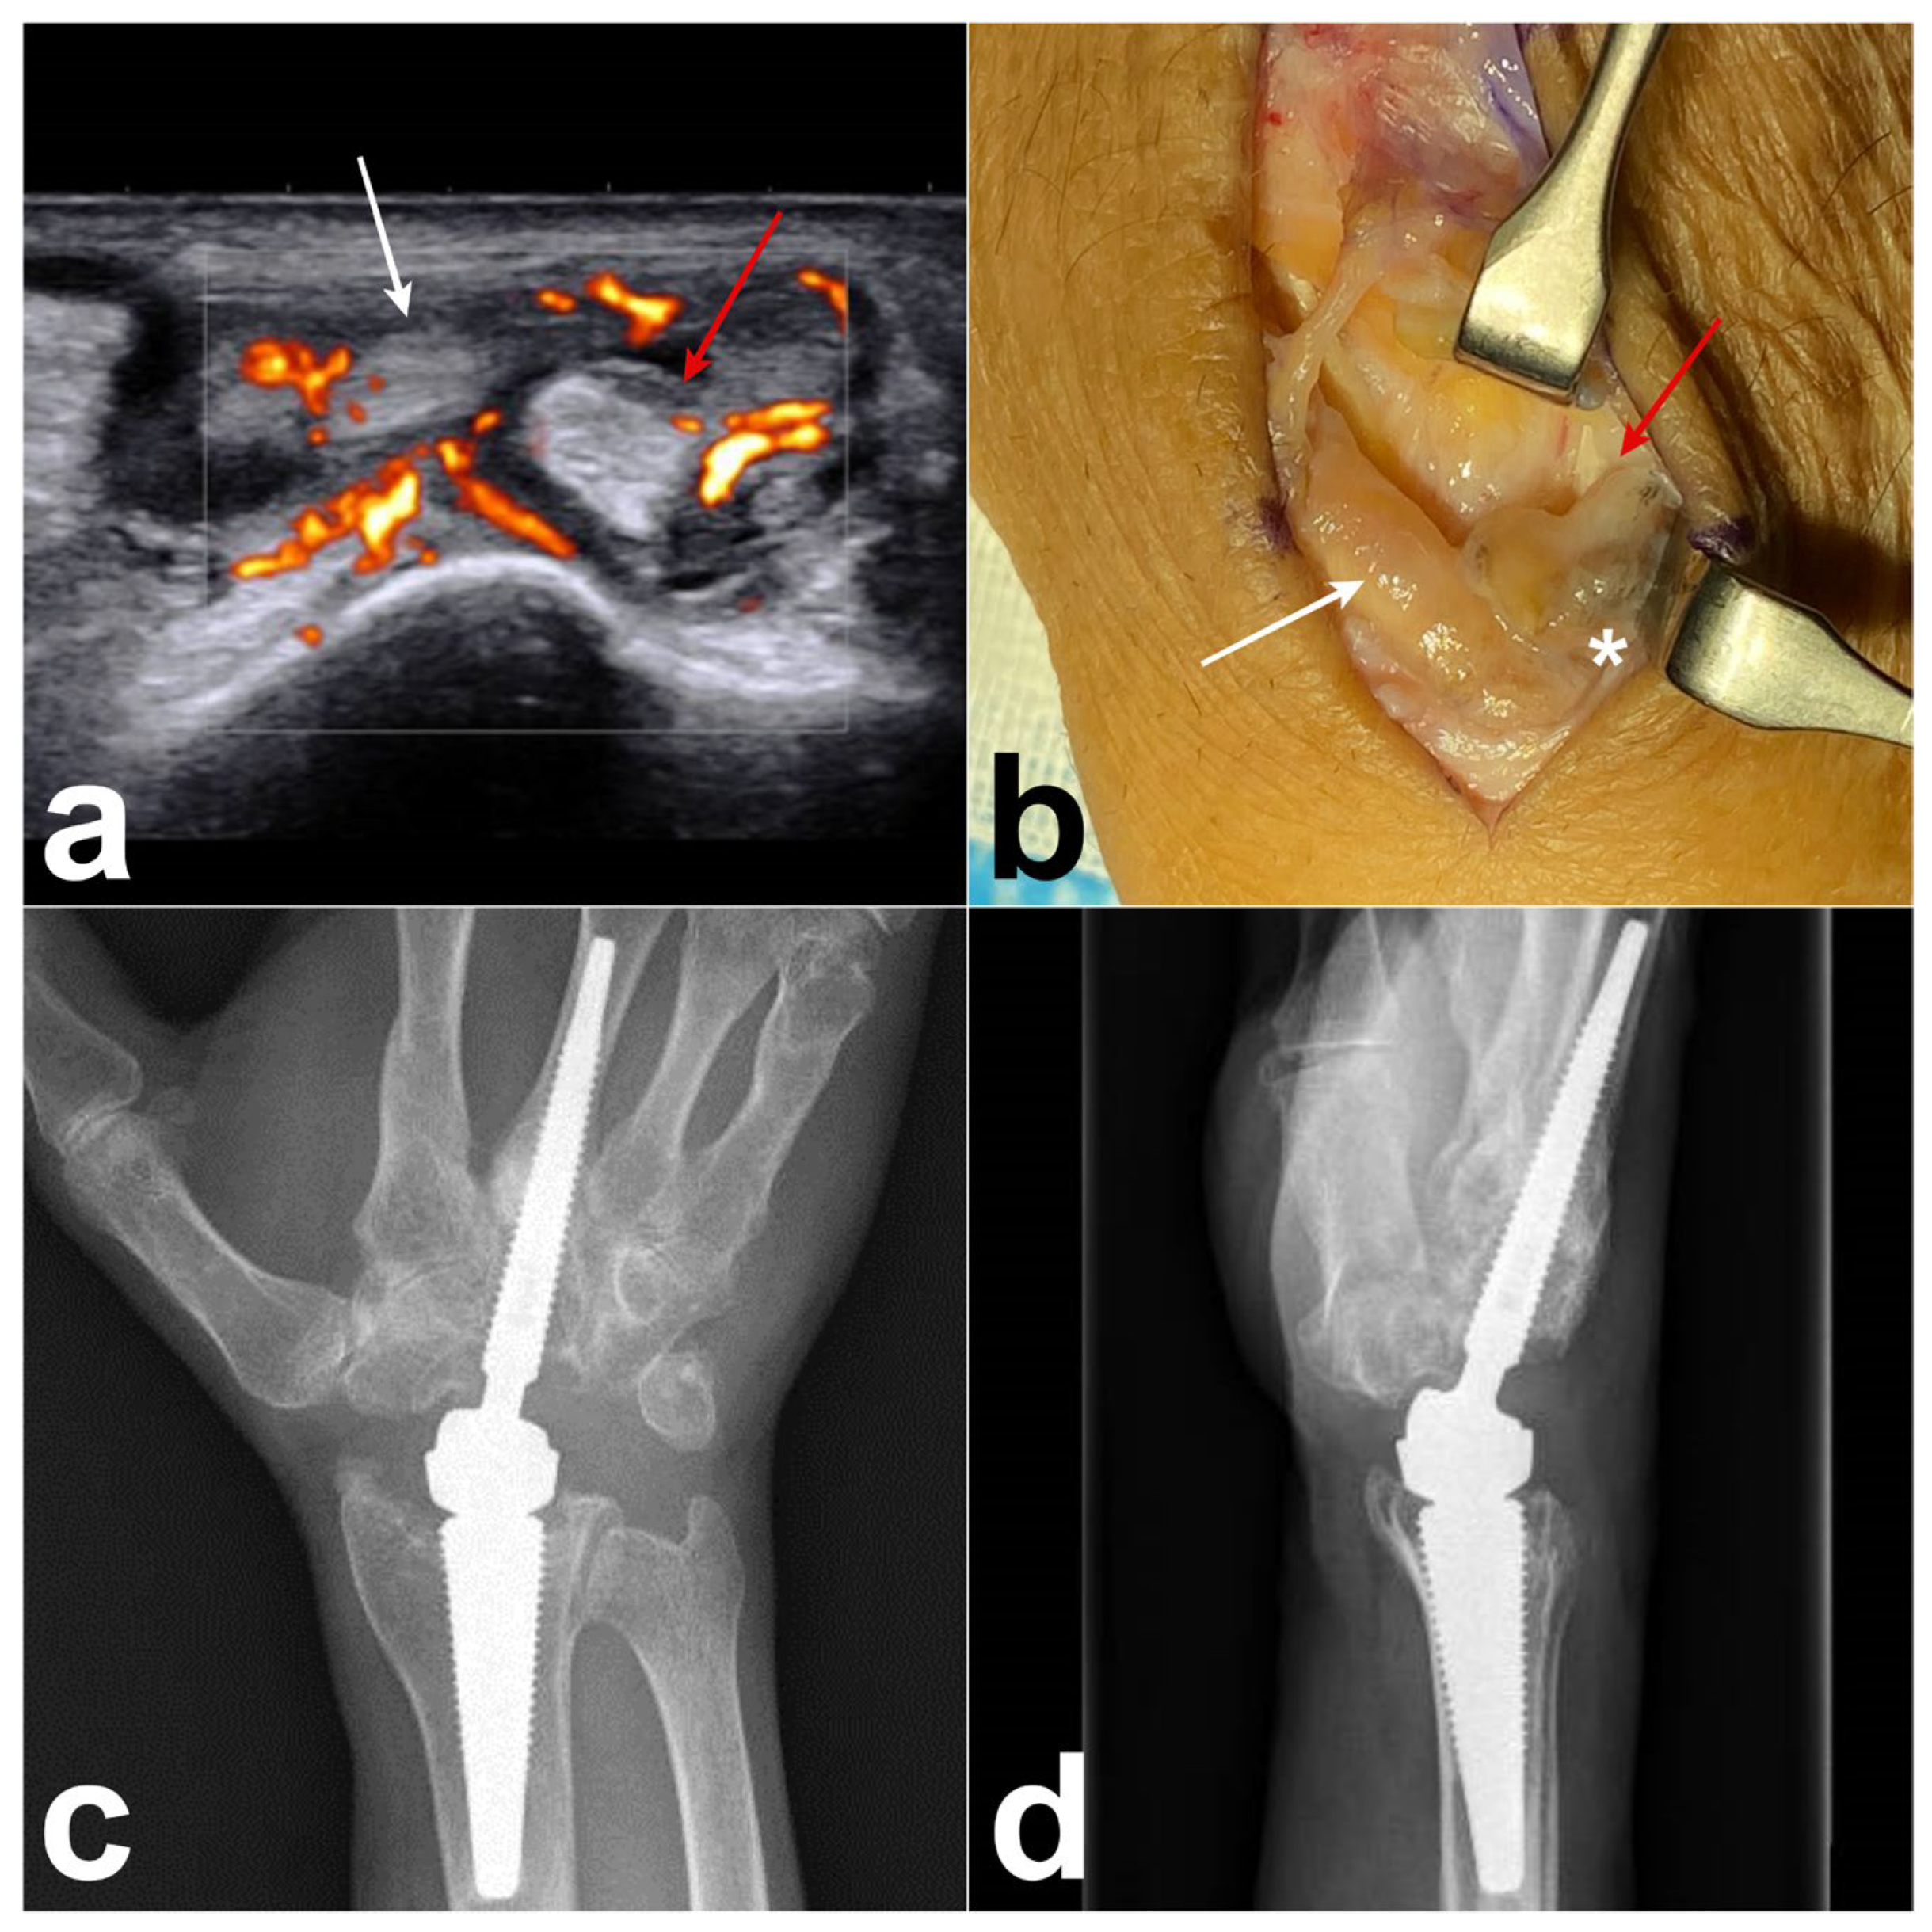

A 64-year-old right-handed man underwent a right wrist arthroplasty (Motec® wrist joint prosthesis; Swemac, Linköping, Sweden) for severe radiocarpal and midcarpal osteoarthritis. One and a half years after the surgery, the patient presented with tenderness and edema on the dorsoradial side of the wrist. Ultrasonography revealed a DIT (Figure 4a) of the right wrist. Revision surgery was performed, revealing the presence of tenosynovitis associated with metallosis of the EPL, ECRB, and ECRL (Figure 4b) and intra-articular metallosis around the prosthesis. Metallosis was confirmed via histopathological examination. After the synovectomy of the radiocarpal joint, we replaced the prosthetic components with a new metal head and changed the CrCo cup to a PEEK cup (Figure 4c,d). Three months after surgery, the dorsal swelling and pain disappeared, and the ultrasound results returned to normal.

Figure 4. Case 2. (a) Ultrasonography reveals tenosynovitis around the EPL (white arrow), ECRB (red arrow), and ECRL. (b) Preoperative photograph showing the presence of tenosynovitis over the EPL (white arrow) and ECRB (red arrow), and associated with metallosis (white asterisk). (c,d) Postoperative radiograph showing the Motec wrist prosthesis with PEEK cup.